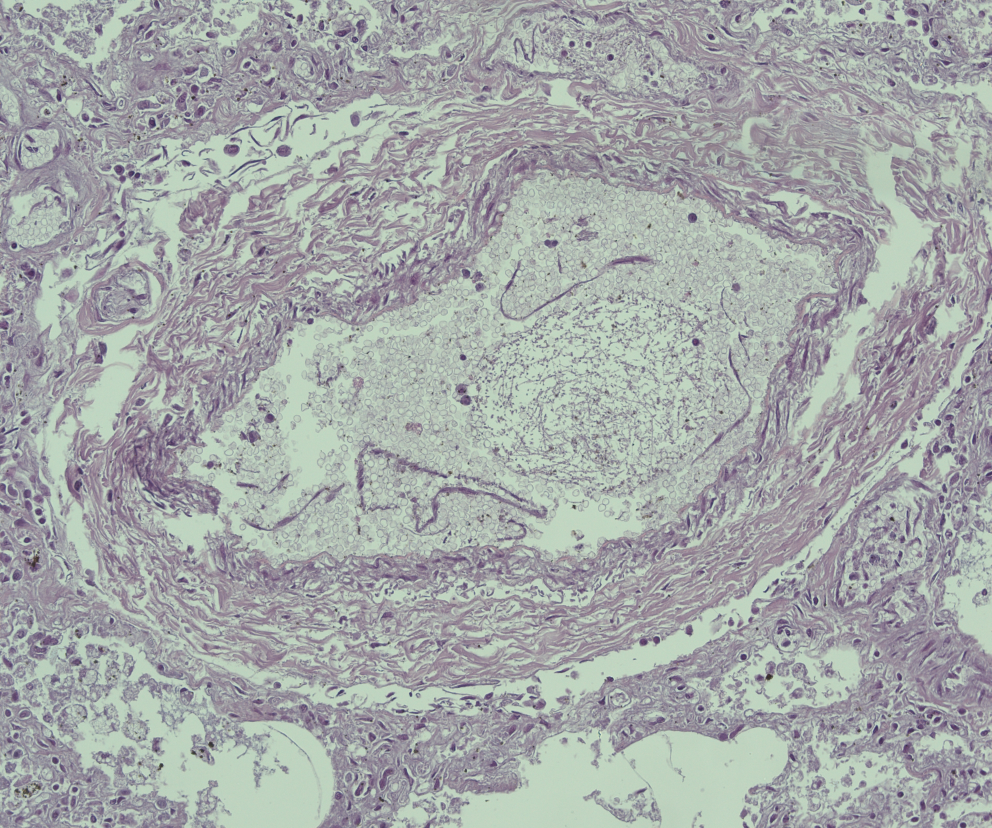

Tissue samples were first dehydrated in graded ethanol, and then clarified in xylene and embedded in paraffin. Paraffin blocks were obtained and cut to a thickness of 4 μm, by a microtome and, finally, and sections were mounted on silane-coated slides (Dako, Glostrup, Denmark) were prepared and stored at the standard temperature room. The sections were then stained with hematoxylin and eosin (H&E). The Zeiss Axioplan (Carl Zeiss, Oberkochen, Germany) was used as an optical microscope, and then images were extracted through the Zeiss AxioCam MRc5 digital camera (Carl Zeiss, Oberkochen, Germany). The heart samples displayed foci of contraction band necrosis, and waviness. Lung sampling showed outbreaks of bronchopneumonia with septic emboli, acute emphysema, and edema (Fig. 2). Brain samples showed signs of stasis and edema. Histological samples of the liver, kidney, pancreas, intestine, spleen and adrenal glands were also performed and did not show any pathological elements.

Fig. 2

H&E 50x. Lung, septic emboli

In this manuscript, SUPC was followed by a 5-month hospitalization in which the infant experienced numerous healthcare-related infections from various microorganisms, including Staphylococcus epidermidis, Staphylococcus Homini, Candida Albicans, and Klebsiella Pneumoniae. Blood cultures were negative for Pneumocystis carinii. The infectious picture was also demonstrated through CT and chest x-ray. However, these infections were treated with appropriate antibiotics after susceptibility testing. After 5 months, laboratory tests were normal and the child did not have any infection but only bacterial contamination. The pulmonary findings examined showed pulmonary bulae. However, it would appear that bulae are attributable more to the long duration of hospitalization and the outcomes of nosocomial pulmonary infections, rather than to the genetic BUB1 mutation. Also Fig. 2 shows “hyphae” attributable to Candida Albicans infection.